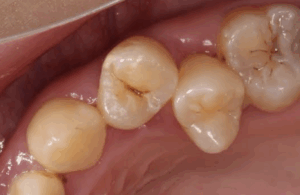

これは、初期虫歯C1(シーワン)です。

細菌により、エナメル質が溶けてしまっています。

なんと、ここでも痛みもなく自覚症状が全然ない状態です。

見た目は、少し茶色くなっていて穴や溝ができてきます。

定期検診に通って頂いていれば、麻酔なしでここの段階で治療することができます😊